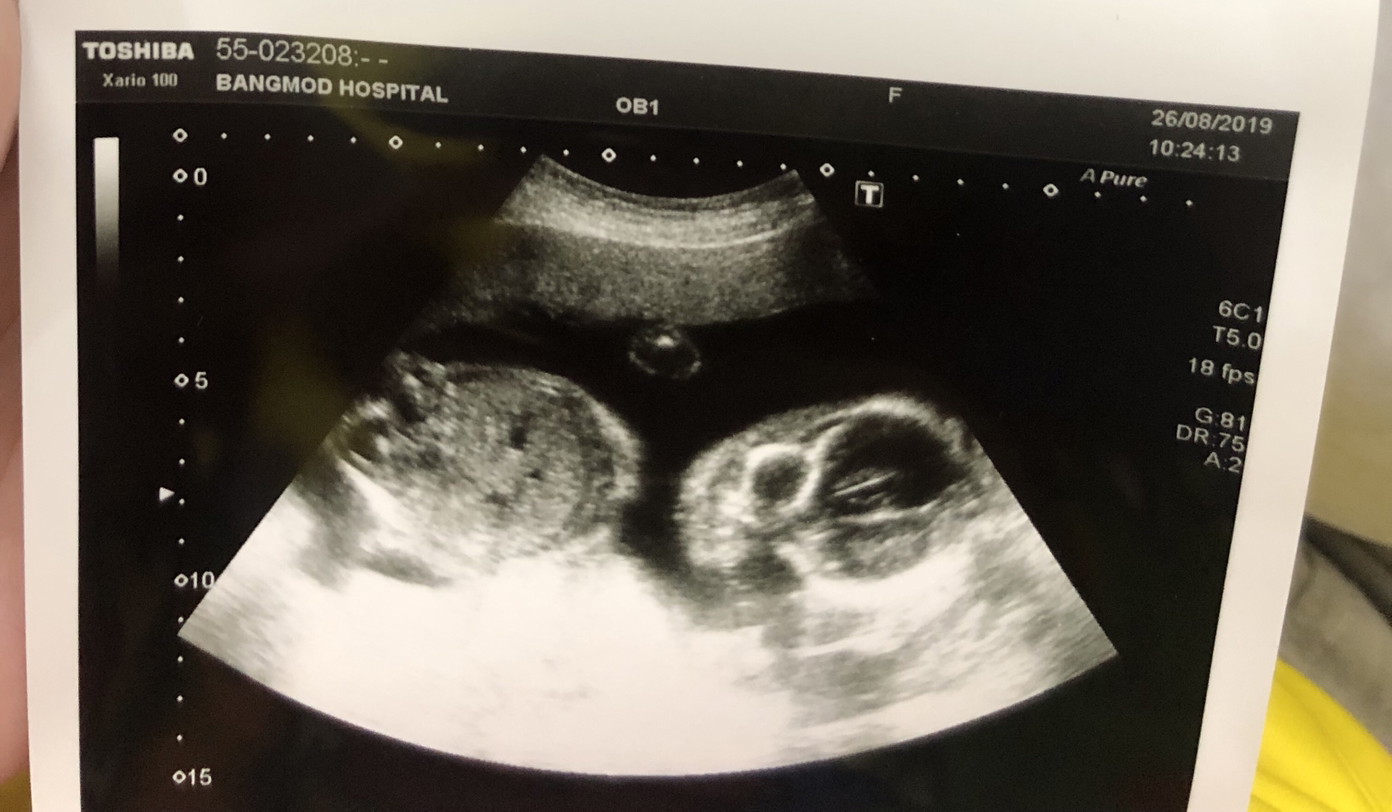

บ้านนี้ก้อลูกชายค่ะ30w++

20 ธันวาคม ค่ะ ผู้ชาย